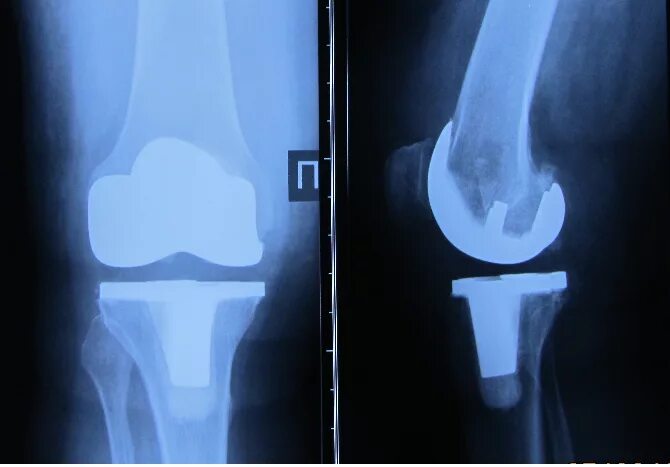

Эндопротез тазобедренного сустава мкб 10